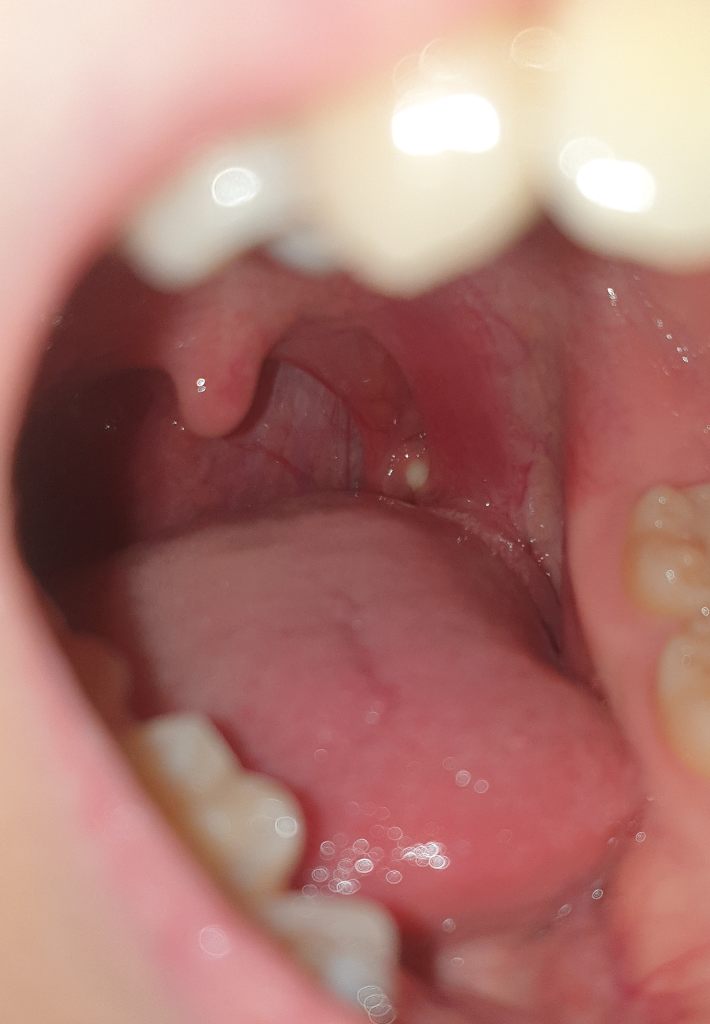

편도에 뭐가 생긴건가요? 하얀색 동그라미

저기에 하얀색 이빨? 같이 뭐가 동그랗게 났는데 편도결석인가요? 아니면 다른 질병인가요?

이걸 치료를 받아야하나요? 만약 치료가 필요하다면 어느 병원을 가야하죠?

• 2번 째 사진

사진만으로는 다소 제한적이나 편도 결석이 생각 됩니다.

편도 결석은 편도 혹은 편도선에 있는 작은 구멍들에 음식물 찌꺼기와 세균이 뭉쳐서 생기는 쌀알 크기의 작고 노란 알갱이를 말하며 이름에 결석이라고 붙어 있지만 대부분 돌처럼 딱딱하지는 않습니다.

저절로 나오기도 하며 흡인 등으로 제거하는 치료를 할 수 있는데, 어느 정도 시간이 지나면 다시 생길 수도 있으며 레이저나 질산은 같은 약물로 편도에 있는 구멍을 막는 치료를 하기도 하지만, 편도 자체를 없애는 편도절제술이 가장 확실한 방법입니다. 그러나 편도결석이 있다고 모두 편도절제술을 시행할 필요는 없고, 수술의 효과와 합병증의 위험을 고려하여야 합니다.

편도염이 있을 때 종종 관찰되는 삼출물로 보입니다. 편도염을 추정할 수 있는 근거가 되는 편이고, 이비인후과에서 확인을 받아보실수 있겠습니다.

• 사진의 소견만으로 정확하게 판단하기는 어렵지만 편도의 석일 가능성이 가장 높아 보입니다. 아니라면 반대로 구내염일 수도 있겠습니다. 일단 상태 평가를 위해서 이비인후과 진료 및 검진을 받아보시길 권고드립니다.